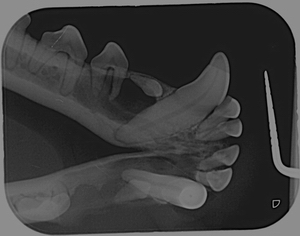

Snímky z intraorálních RTG. Černé oblasti pod prvními premoláry (P1) z obou stran jsou zubní cysty. Základy pro oba P1 jsou vytvořeny, avšak ani jeden z nich se neprořezal. Druhý premolár (P2) na pravé straně zcela chybí.

5.jpg

Z levé strany spodní čelisti můžeme vidět, že zde chybí zub. Trvalý zub se neprořezal.